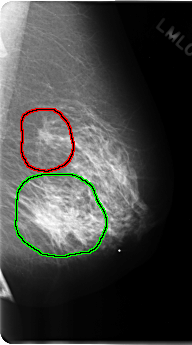

FILE: C_0191_1.LEFT_CC.OVERLAY

TOTAL_ABNORMALITIES 2

ABNORMALITY 1

LESION_TYPE MASS SHAPE IRREGULAR MARGINS ILL_DEFINED

ASSESSMENT 5

SUBTLETY 5

PATHOLOGY MALIGNANT

TOTAL_OUTLINES 1

ABNORMALITY 2

ASSESSMENT 4

SUBTLETY 4